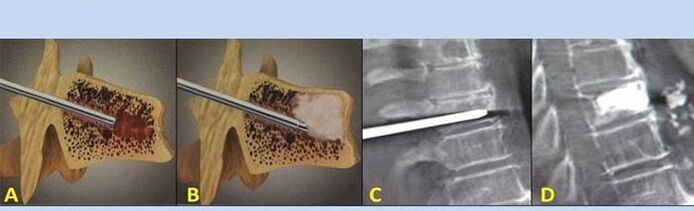

- Nukleoplastika - lülidevahelise ketta südamiku eemaldamine. Operatsioon leevendab survet närvilõpmetele.

- Vertebroplastika punktsioon - selgroolülide stabiliseerimise meetod. Protseduuri käigus täidab arst lülisamba õõnsused luutsemendiga.